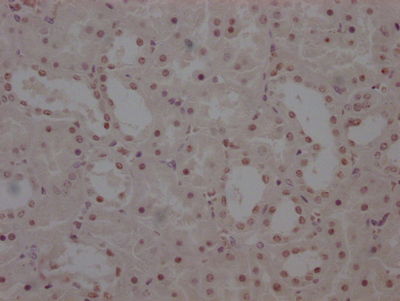

IHC image of CSB-PA03099A0Rb diluted at 1:400 and staining in paraffin-embedded human colon cancer performed on a Leica BondTM system. After dewaxing and hydration, antigen retrieval was mediated by high pressure in a citrate buffer (pH 6.0). Section was blocked with 10% normal goat serum 30min at RT. Then primary antibody (1% BSA) was incubated at 4°C overnight. The primary is detected by a biotinylated secondary antibody and visualized using an HRP conjugated SP system.